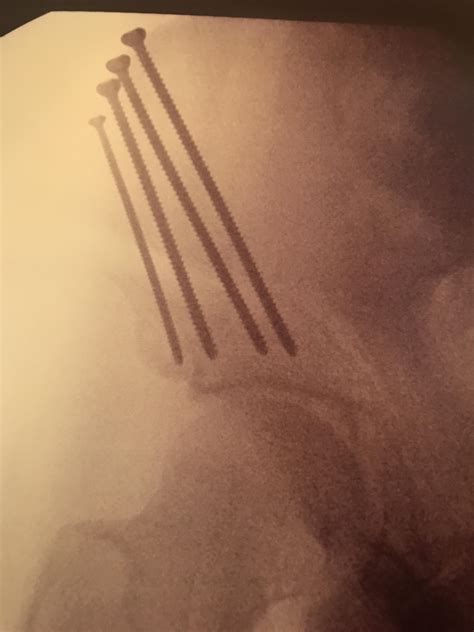

Revision Hip Surgery – Knee and Hip Website

Revision Hip Surgery – Knee and Hip Website